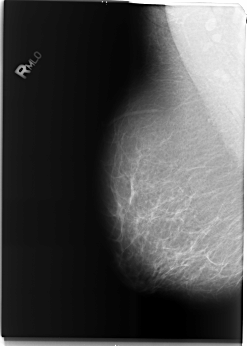

B_3494_1.RIGHT_MLO

RIGHT_MLO LINES 5880 PIXELS_PER_LINE 4184 BITS_PER_PIXEL 12 RESOLUTION 50 NON_OVERLAY